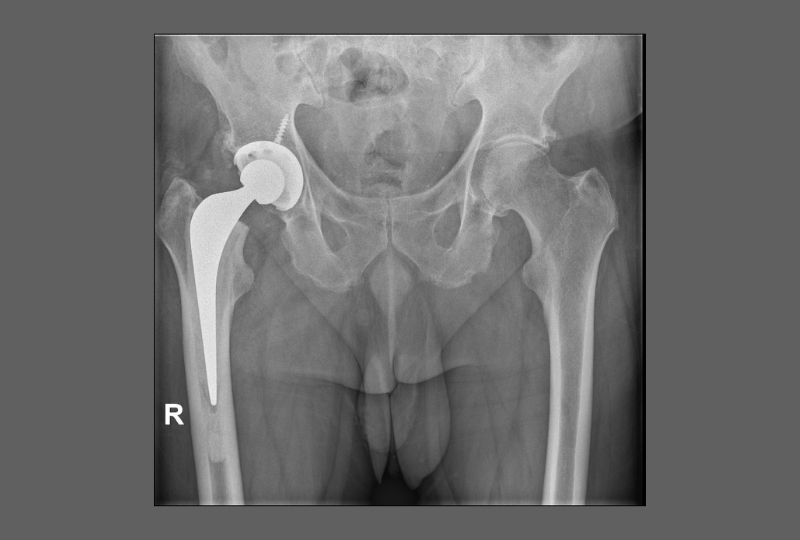

robotic assisted surgery hip replacement example

Example of Robotic Assisted Surgery